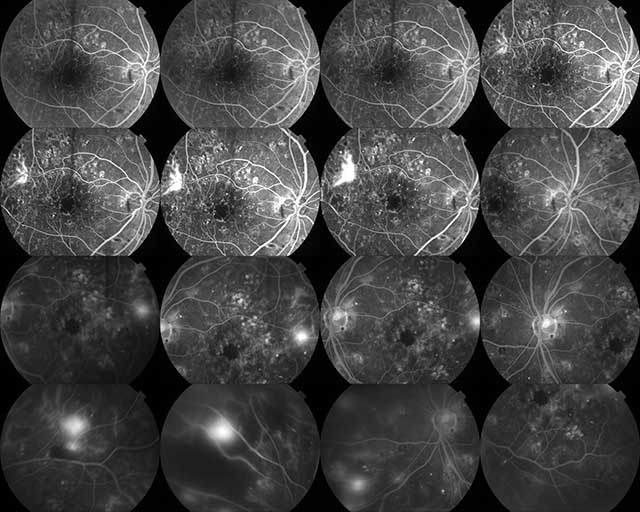

Φλουοροαγγειογραφία: Η «Χαρτογράφηση» των Αγγείων του Οφθαλμού

Η φλουοροαγγειογραφία αποτελεί μια ανεκτίμητη διαγνωστική εξέταση για την αξιολόγηση της ακεραιότητας των αιμοφόρων αγγείων του αμφιβληστροειδούς. Μας επιτρέπει να εντοπίσουμε βλάβες που δεν είναι ορατές με την απλή κλινική εξέταση.

Η φλουοροαγγειογραφία αποκαλύπτει με ακρίβεια:

Διαρροές υγρού ή αίματος.

Οίδημα στην ωχρά κηλίδα.

Ανώμαλα νεοαγγεία (όπως στην υγρή μορφή της Ηλικιακής Εκφύλισης).

Περιοχές ισχαιμίας (κακίας κυκλοφορίας), συχνές σε διαβητικούς ασθενείς.